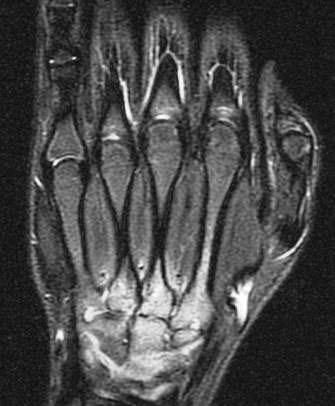

14 y/o with history of bilateral wrist pain.

His carries a known diagnosis of Juvenile Rheumatoid Arthritis. (RID3610) New term is JIA. He has failed steroid therapy and methotrexate. Currently on humira. R/O osseous change. Its ruled in. Reference article.

Juvenile idiopathic arthritis